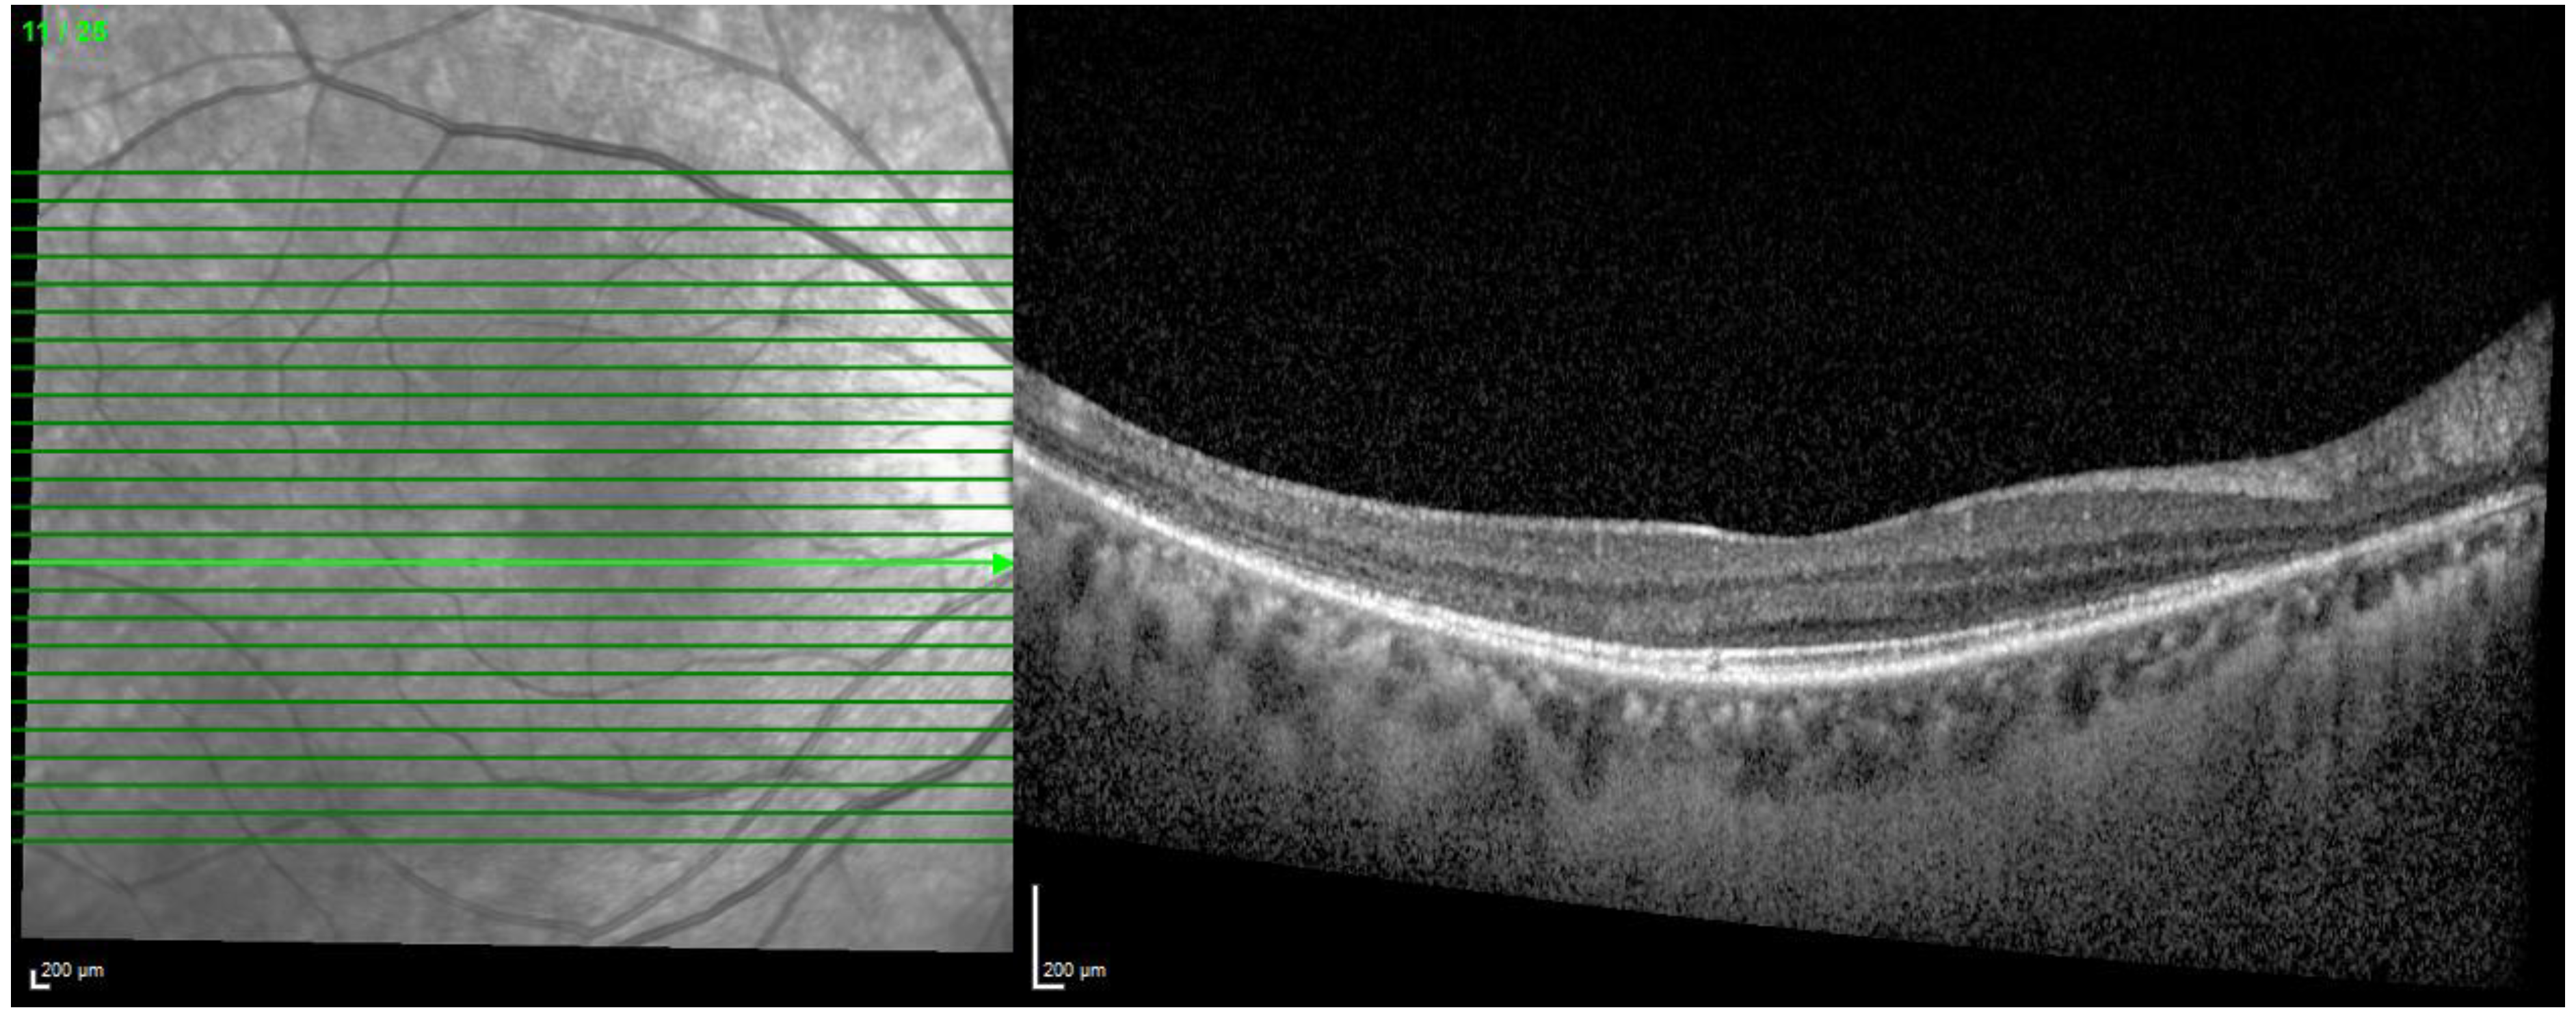

2. Standard Retinal Imaging for HCQ Retinopathy

2.1. Optical Coherence Tomography

3.1. Novel OCT Analysis

3.1.1. Retinal Changes

Outer RT

3.1.4. En Face OCT